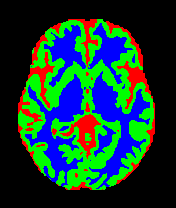

• MRBrainS13 [35]: From the MICCAI 2013 challenge, this dataset contains multi-sequence scans of 20 subjects acquired on a 3.0T Philips Achieva scanner. It provides T1 (TR: 7.97.9 ms, TE: 4.54.5 ms), T1-IR, and T2-FLAIR sequences. All scans are co-registered and bias-corrected with a voxel spacing of 0.96×0.96×3.000.96\times 0.96\times 3.00 mm. We utilize the provided labels for CSF, GM, and WM segmentation.

7 Qualitative Evaluation

Fig. 8 and Fig. 10 provide qualitative comparisons on the OASIS-1 and MRBrainS13 datasets, respectively. It is visually evident that the baseline predictions (c) and standard augmentations (e.g., (d), (g), (i)) frequently suffer from noisy artifacts, blurred boundaries, and mis-segmentation of intricate anatomical structures. In stark contrast, our ”Ours+” enhanced methods (e.g., (e), (h), (k)) consistently produce segmentation maps that are visibly cleaner, more spatially coherent, and demonstrate significantly sharper adherence to the Ground Truth (b). This superior fidelity is particularly noticeable in the complex sulcal patterns and holds true across all three backbones (rows), confirming that our framework yields more robust and anatomically plausible results.